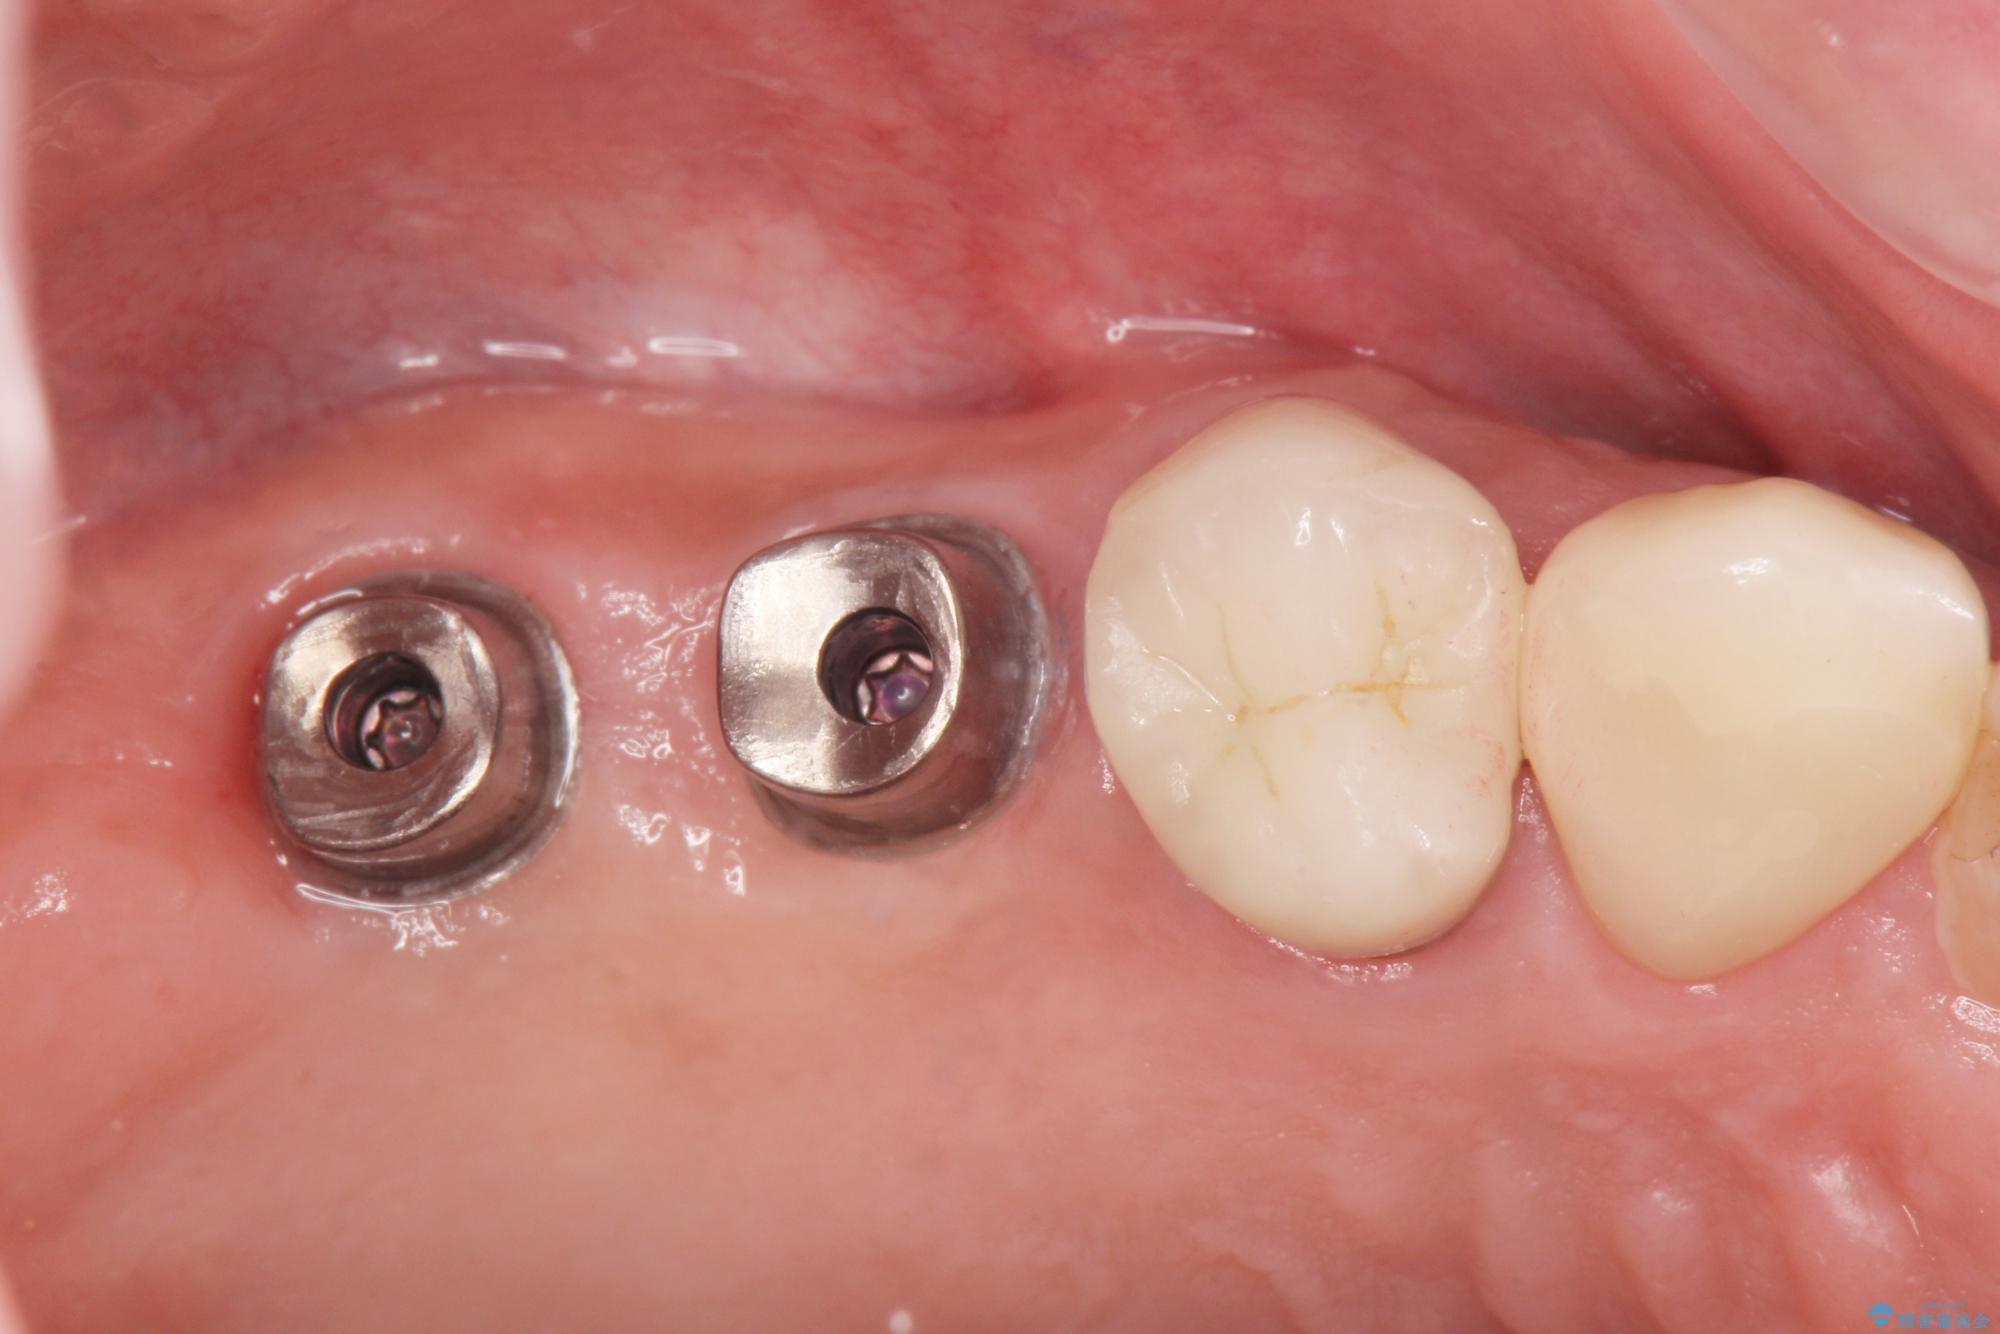

- 歯を抜いたまま放置してしまい、「やはりしっかりと噛めるような状態にしてほしい」とインプラント治療を希望され来院されました。

人工歯根であるインプラントを埋入することで奥歯でまたしっかりと噛める咬合機能を回復します。

- 88万円(インプラント×2・仮歯×2・チタンカスタムアバットメント×2・ジルコニアクラウン×2)費用は治療当時の料金となります